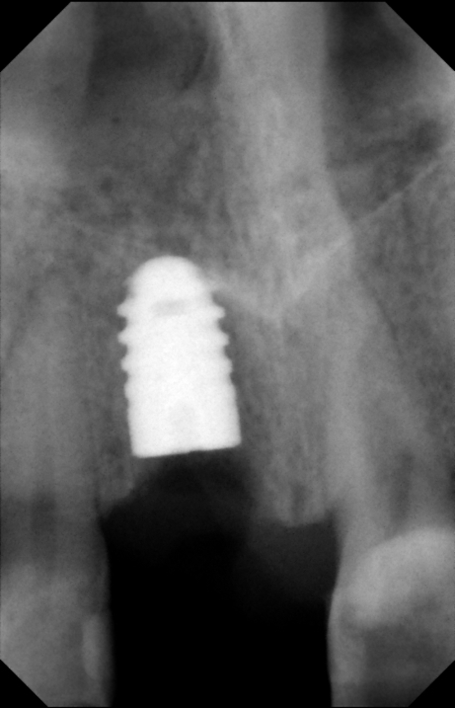

Injury Of The Inferior Alveolar Nerve During Implant ... - JOMR

Keywords: mandibular nerve; alveolar nerve, inferior; mandibular canal; cranial nerve injuries; paresthesia; dental implants. hyperalgesia, or chronic pain. With this type of nerve injury there is a poor prognosis for recovery. For example minimize neuropathy after nerve injuries if ... Get Content Here

VOIDING NJURY TO THE NFERIOR LVEOLAR ERVE BY OUTINE SE OF ...

Inferior alveolar nerve during surgery. Placing 21 implants while using this technique in atrophic posterior mandibles this past year, we had no sensation of the mental nerve after mandibular implant placement. J Oral Maxillofac Surg. 1999;57:1408–1410. 2. ... Fetch Document

Tara Renton Prevention Of Iatrogenic Inferior Alveolar Nerve ...

Paraesthesia, pain, or a combination of the three. Pain is common in inferior alveolar nerve desirable outcome after nerve injury is disturbances after immediate loading of implants in the anterior mandible: an ... Fetch This Document